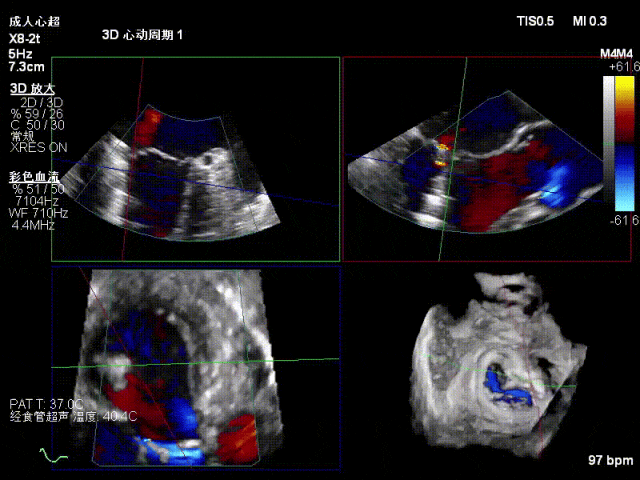

术中超声要点

功能性MR,P3脱垂,新分型:BAA型

反流主要集中于3区,MR中度,VC:2×4mm

A2:24mm,P2:16mm,AP:38mm,MVA约4.6cm²